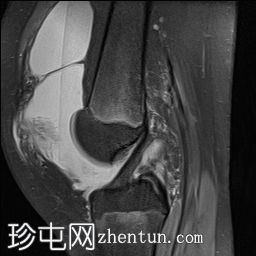

矢状位

T1加权像

关节内大量积血,可见血细胞比容增高征。股骨外侧髁前部及髌骨内侧可见挫伤性微骨折。髌骨内侧支持带及髌股内侧韧带水肿增厚。髌骨内侧关节面下关节软骨浸润,提示I期骨软骨损伤。

髌骨外侧隐窝可见游离体,其信号强度与关节软骨一致,提示髌骨关节软骨外剥离损伤。股骨滑车和股骨关节软骨正常。

胫骨近端和腓骨骨骺以及股骨远端延伸至干骺端的骨骺周围可见局灶性骨髓水肿。这些提示存在局灶性骨骺周围水肿区。

十字韧带和侧副韧带正常。半月板正常。股四头肌腱和髌腱正常。

该病例具有短暂性髌骨外侧脱位复位损伤的特征性表现,包括预期的骨挫伤模式、内侧髌骨支持带/内侧髌股韧带损伤、髌骨骨软骨损伤以及髌骨软骨游离体。